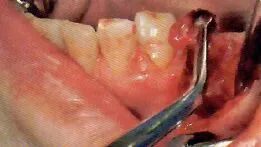

切开线设计(有残根的情况)

务必保证切开线区域的视的野晰度(切开前要吸引唾液,切开过程中要吸引血液)

切开前,一定要将切开线区域的唾液吸引干净。如果切开区域有唾液残留的话,会造成医生无法找到切开线路。切开时,从切开线区域会有血液溢出。将吸唾器放置到出血点,正确找到出血点才能更加有效的将溢出的血液吸引干净。